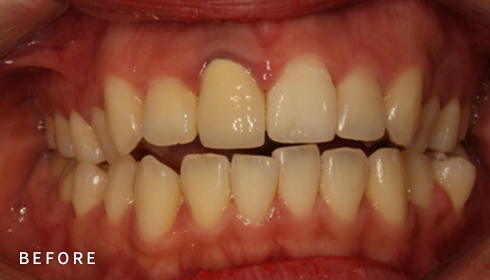

비발치 덧니 교정

덧니고민, 비발치로 교정하세요

악궁 확장, 미니 스크류, 치간 삭제 등 다양한 방법을 활용해 가능한 한

발치를 피하고, 자연스럽고 만족스러운 결과를 얻을 수 있도록

정밀하게 계획하고 진료합니다. 발치 여부가 애매한 경우,

‘레벨링 후 재평가’ 과정을 거쳐 비발치를 우선 고려합니다.